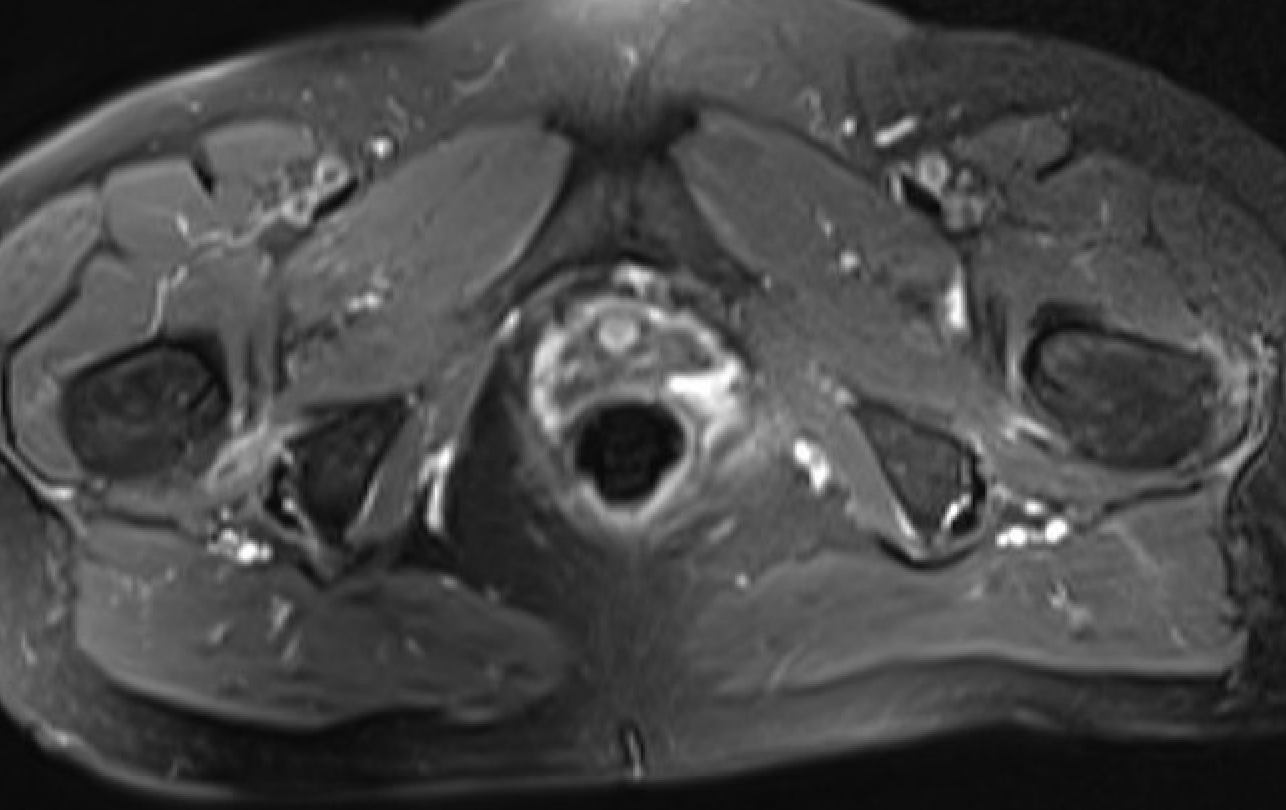

MRI

Reduced ischiofemoral space - distance between the lesser trochanter and the ischial tuberosity

Reduced quadratus femoris space - distance between hamstring tendon and iliopsoas

Inflammation / edema in quadratus femoris +/- fatty degeneration

Singer et al Skeletal Radiol 2015

- systematic review of 190 hip MRI of patients with ischiofemoral impingement

- compared to controls

- ischiofemoral space < 15 mm: sensitivity 77%, specificity 81%, accuracy 78%

- ischiofemoral space < 10 mm: sensitivity 79%, specificity 74%, accuracy 77%.